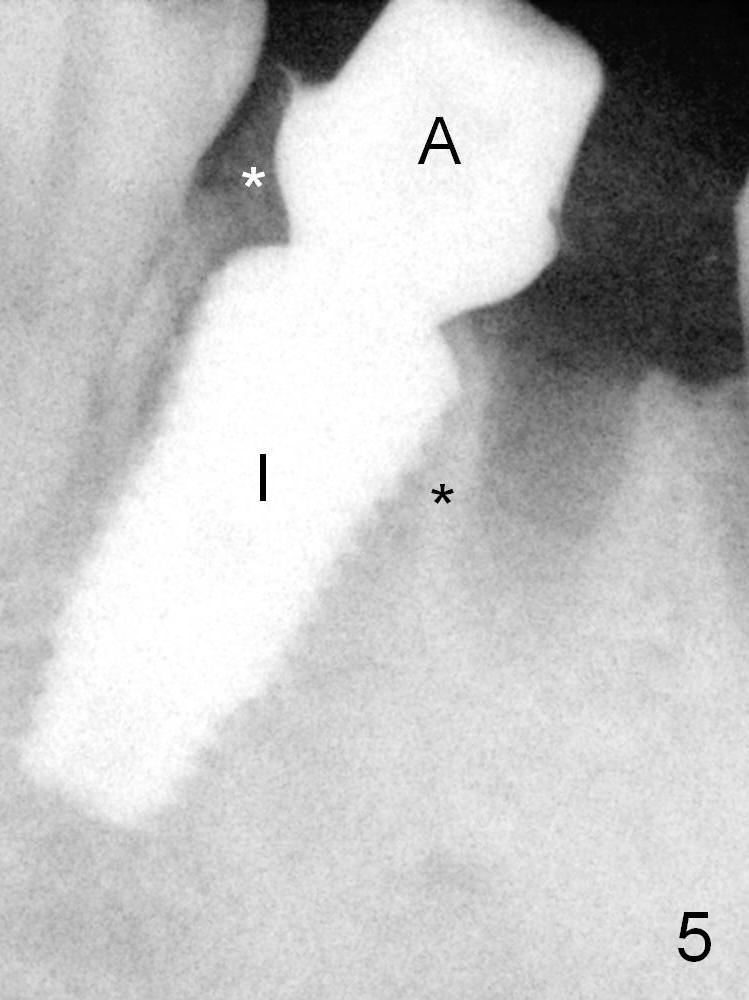

Off axial placement of the implant (Fig.5 I) and abutment (A) is striking in the immediately postop PA (Fig.5).  Black *: septum; white *: bone graft.

In other word, the implant is placed mesially.  There would be a problem if the patient wanted to move #20 distally orthodontically.